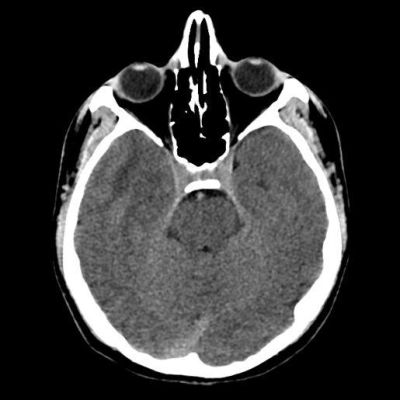

- A) Sağ temporal lob anteromedialinde silik sınırlı BT’de hipodens (ok), MRG’de T2AG ve FLAIR hiperintens (oklar), T1AG izo-hipointens (ok) sinyal özelliğinde ekspansil kitlesel lezyon izlenmektedir.

- BT: Spesifik olmayan kitle bulgularıdır. İzo-hipodens olarak izlenir. Kitle %35 oranında kalsifikasyon gösterebilir. Olgumuzda kalsifikasyon izlenmemiştir. Kemik remodelasyonu da eşlik edebilir.